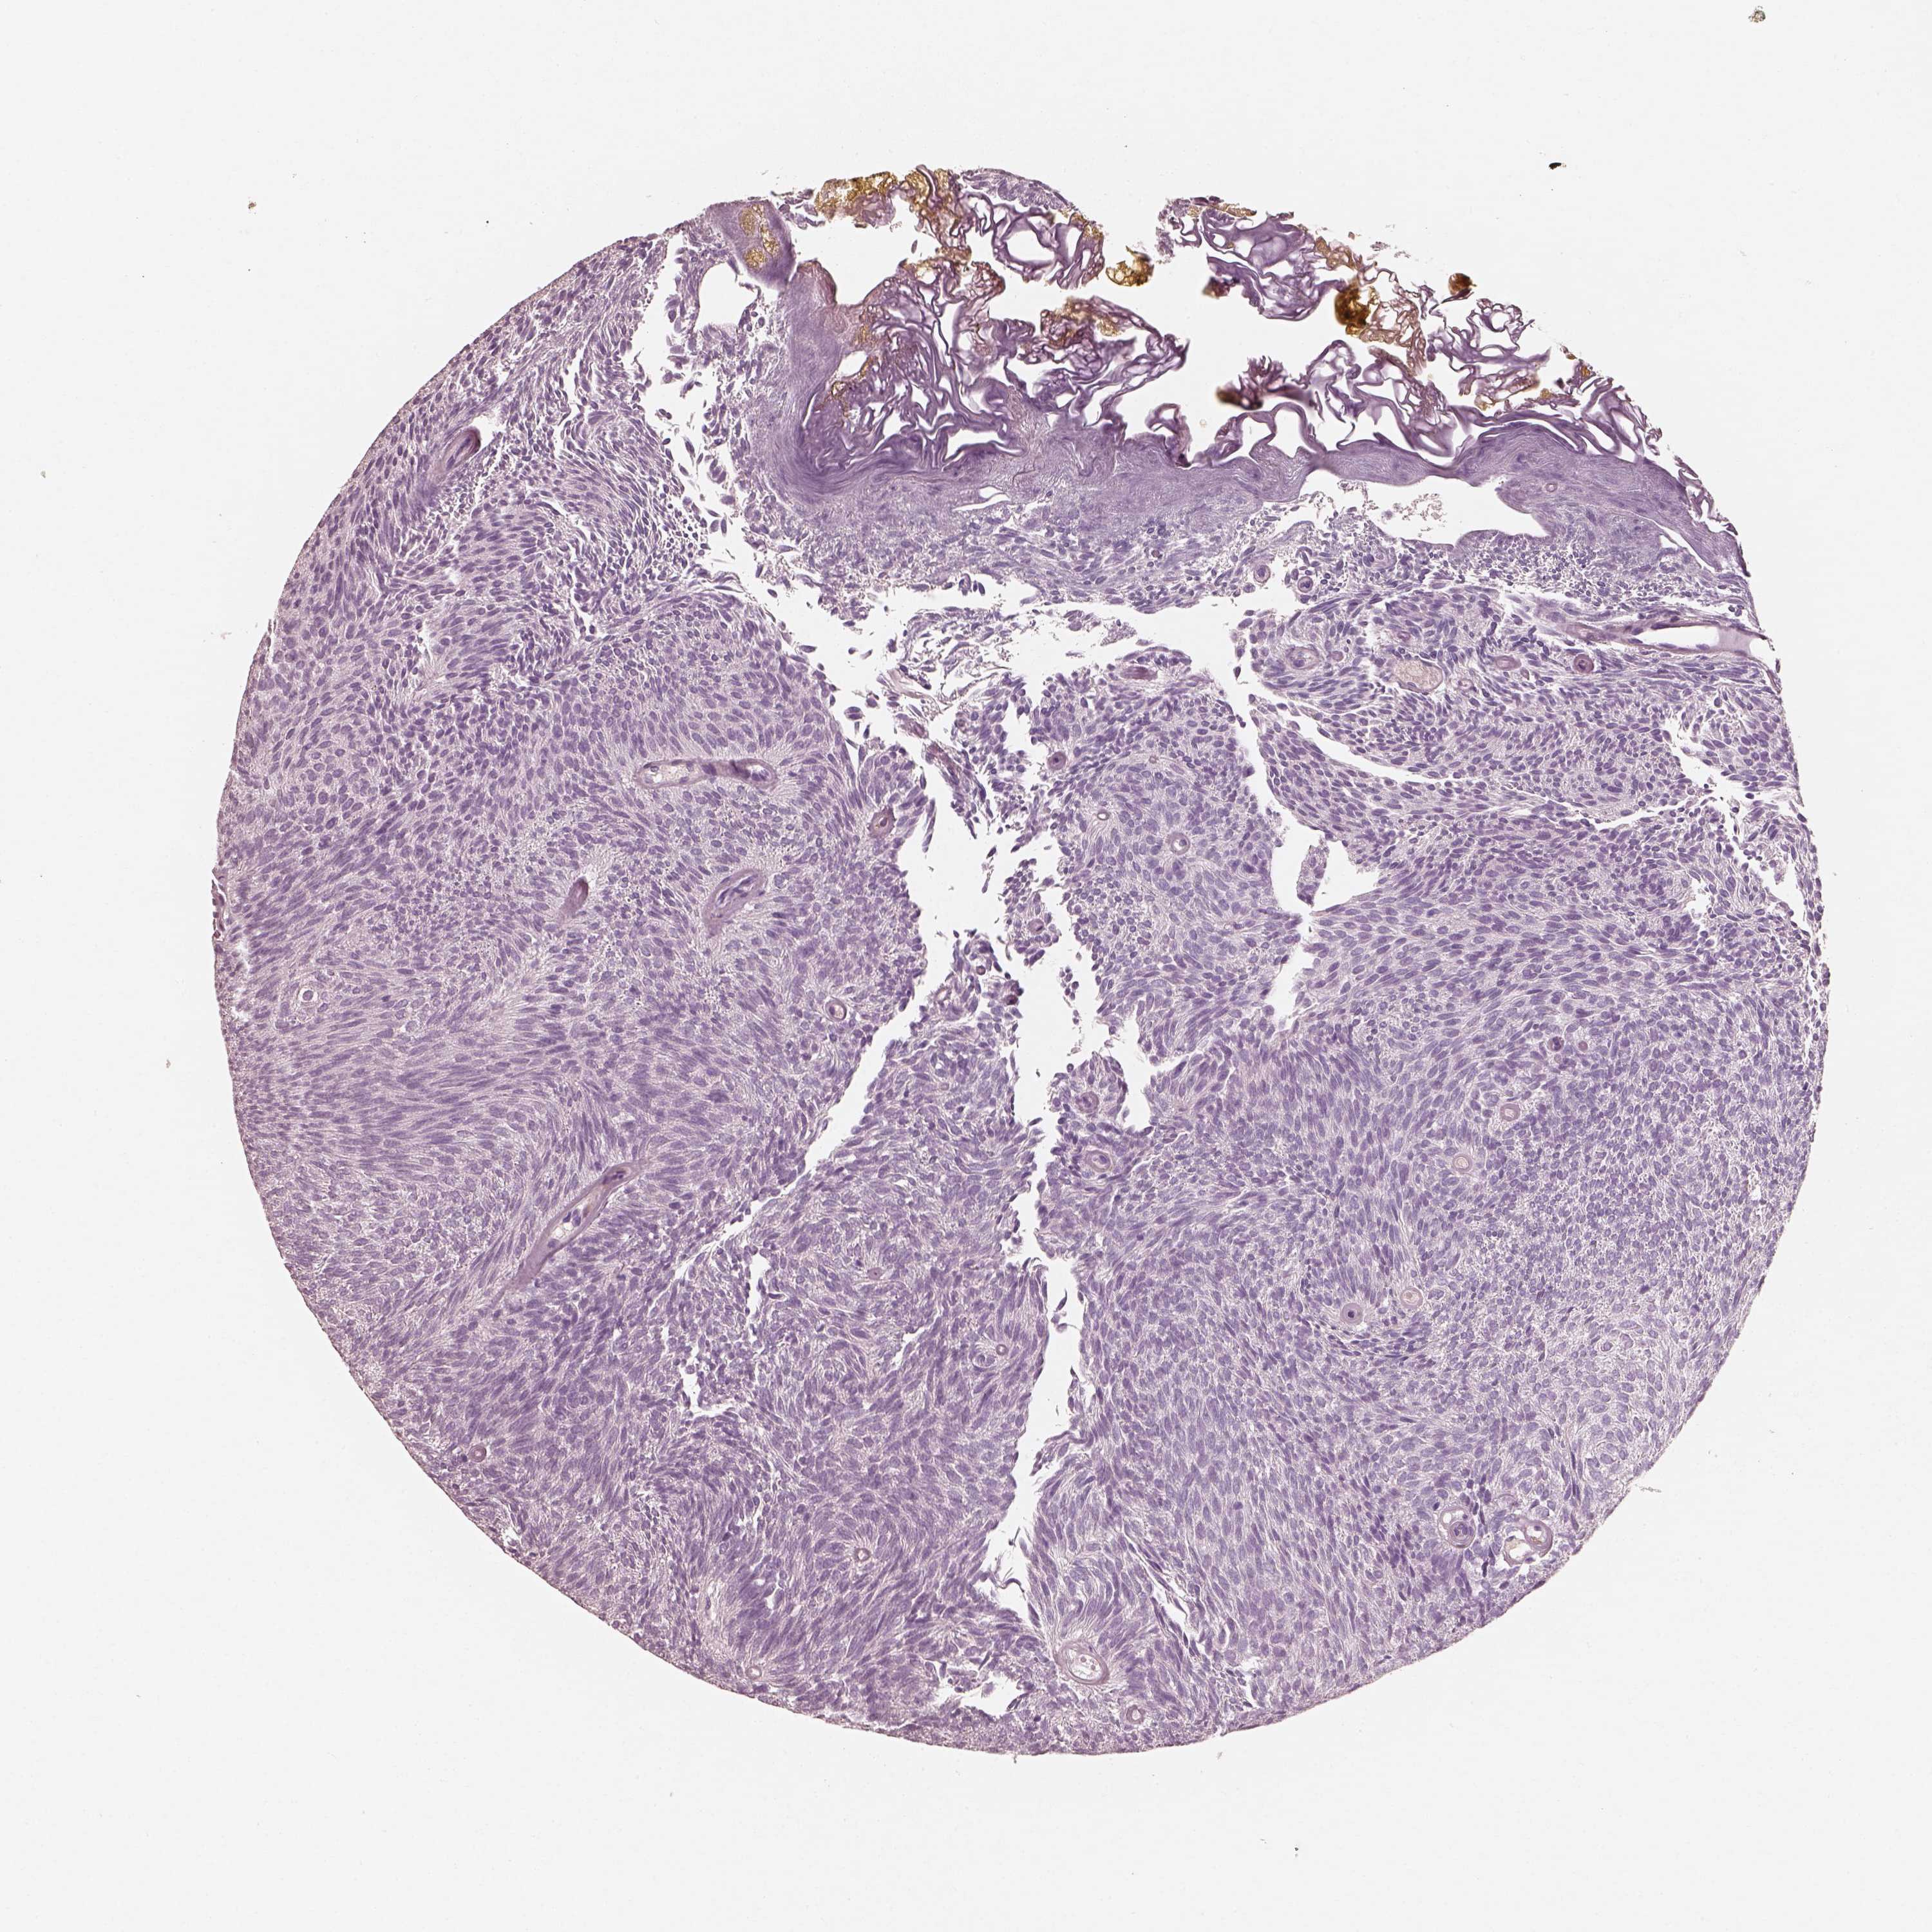

UROTHELIAL CANCER - Protein expressioni

A mouse-over function shows sample information and annotation data. Click on an image to view it in a full screen mode. Samples can be filtered based on level of antibody staining by selecting one or several of the following categories: high, medium, low and not detected. The assay and annotation is described here.

Note that samples used for immunohistochemistry by the Human Protein Atlas do not correspond to samples in the TCGA dataset.

Antibody stainingi

Antibody staining in the annotated cell types in the current human tissue is reported as not detected, low, medium, or high, based on conventional immunohistochemistry profiling in selected tissues. This score is based on the combination of the staining intensity and fraction of stained cells.

Each image is clickable and will lead to virtual microscopy that enables deeper exploration of all samples and also displays staining intensity scores, fraction scores and subcellular localization as well as patient and tissue information for each sample.

Antibody HPA059546

Staining

High

Medium

Low

Not detected

Intensity

Strong

Moderate

Weak

Negative

Quantity

>75%

75%-25%

<25%

None

Location

Nuclear

Cytoplasmic/membranous

Cytoplasmic/membranous,nuclear

Urothelial carcinoma, High grade

Urothelial carcinoma, Low grade